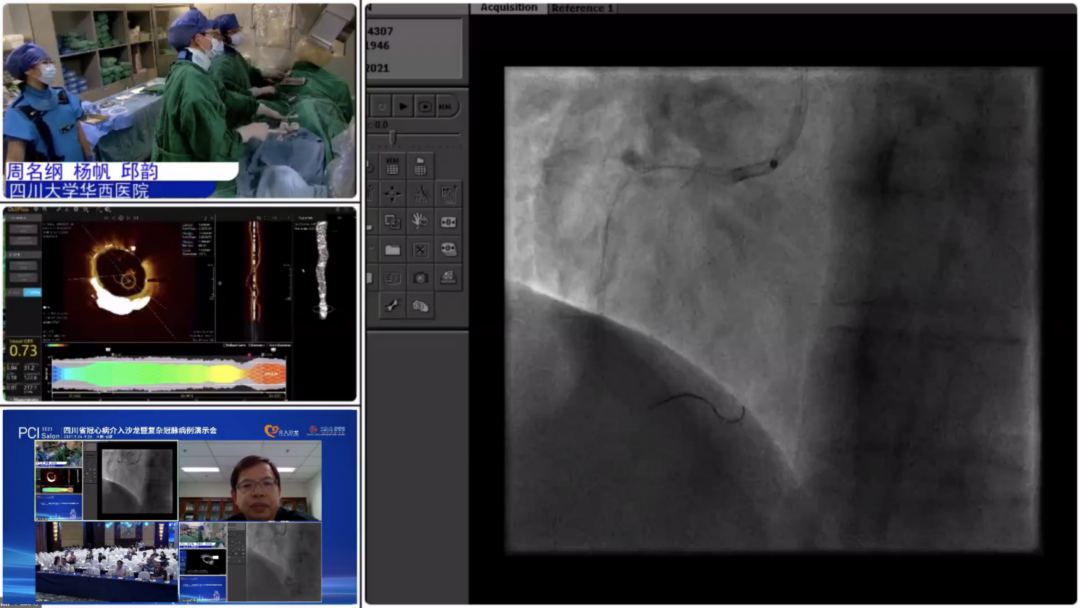

9月25日,大会隆重开幕,大会执行主席、四川大学华西医院贺勇教授主持,大会创始人及名誉主席、四川大学华西医院心内科黄德嘉教授,北京力生心血管健康基金会管廷瑞理事长,大会主席、四川大学华西医院陈茂教授,大会创始人及名誉主席东莞康华医院贾国良教授等多位专家领导分别以线上、线下参会形式共同出席开幕式,并为大会开幕致辞。随后,来自全国多地的冠脉领域资深术者通力配合,带来了11场极具难度和技巧的复杂冠脉病例手术演示及微课讲座。同期进行的护理及技术人员论坛、冠脉腔内影像与生理学论坛、冠心病诊疗论坛、降脂治疗论坛&心衰药物进展论坛、血栓抽吸、药物球囊、愈合型支架等专题学术内容应接不暇、精彩纷呈。